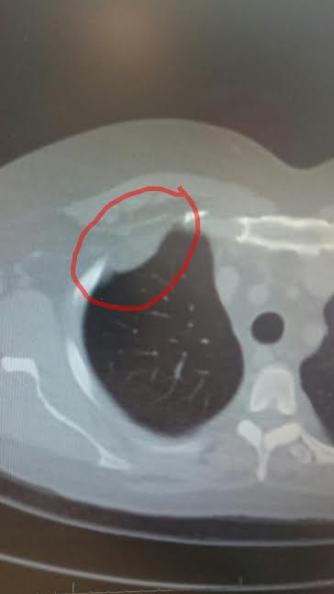

Omdat Ger er vorige keer niet bij was,laat hij de scan zien en mag ik een foto ervan maken..

Ger zegt is dat niet dezelfde plaats als waar de vorige tumor zat..?

Ja,het zit op dezelfde plek als waar ze de vorige tumor met longkwab hebben verwijderd!!!

Best grote plek eigenlijk........zie foto